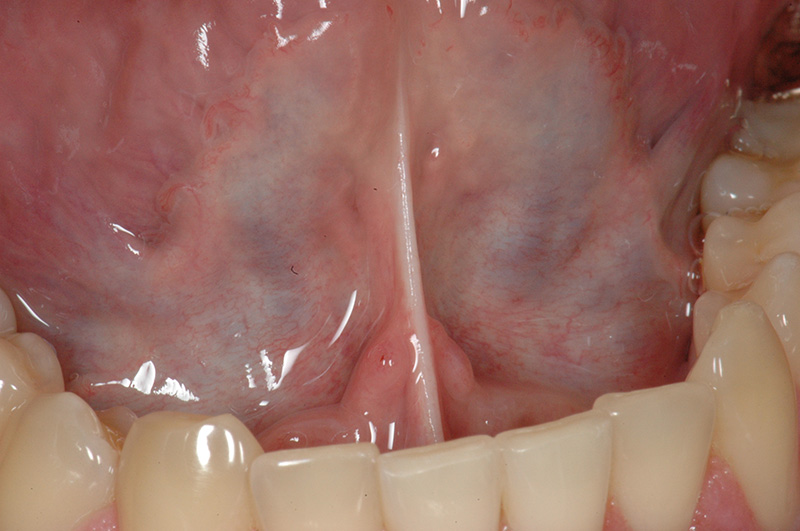

A frenulectomy (also called a frenectomy) is a minor procedure that removes or releases a restrictive frenulum — the small band of tissue connecting the lips or tongue to the mouth. While everyone has frenula, sometimes they can be too short or tight, limiting normal movement.

- Tongue-tie (Ankyloglossia): Caused by a tight lingual frenulum, restricting the tongue’s ability to move freely.